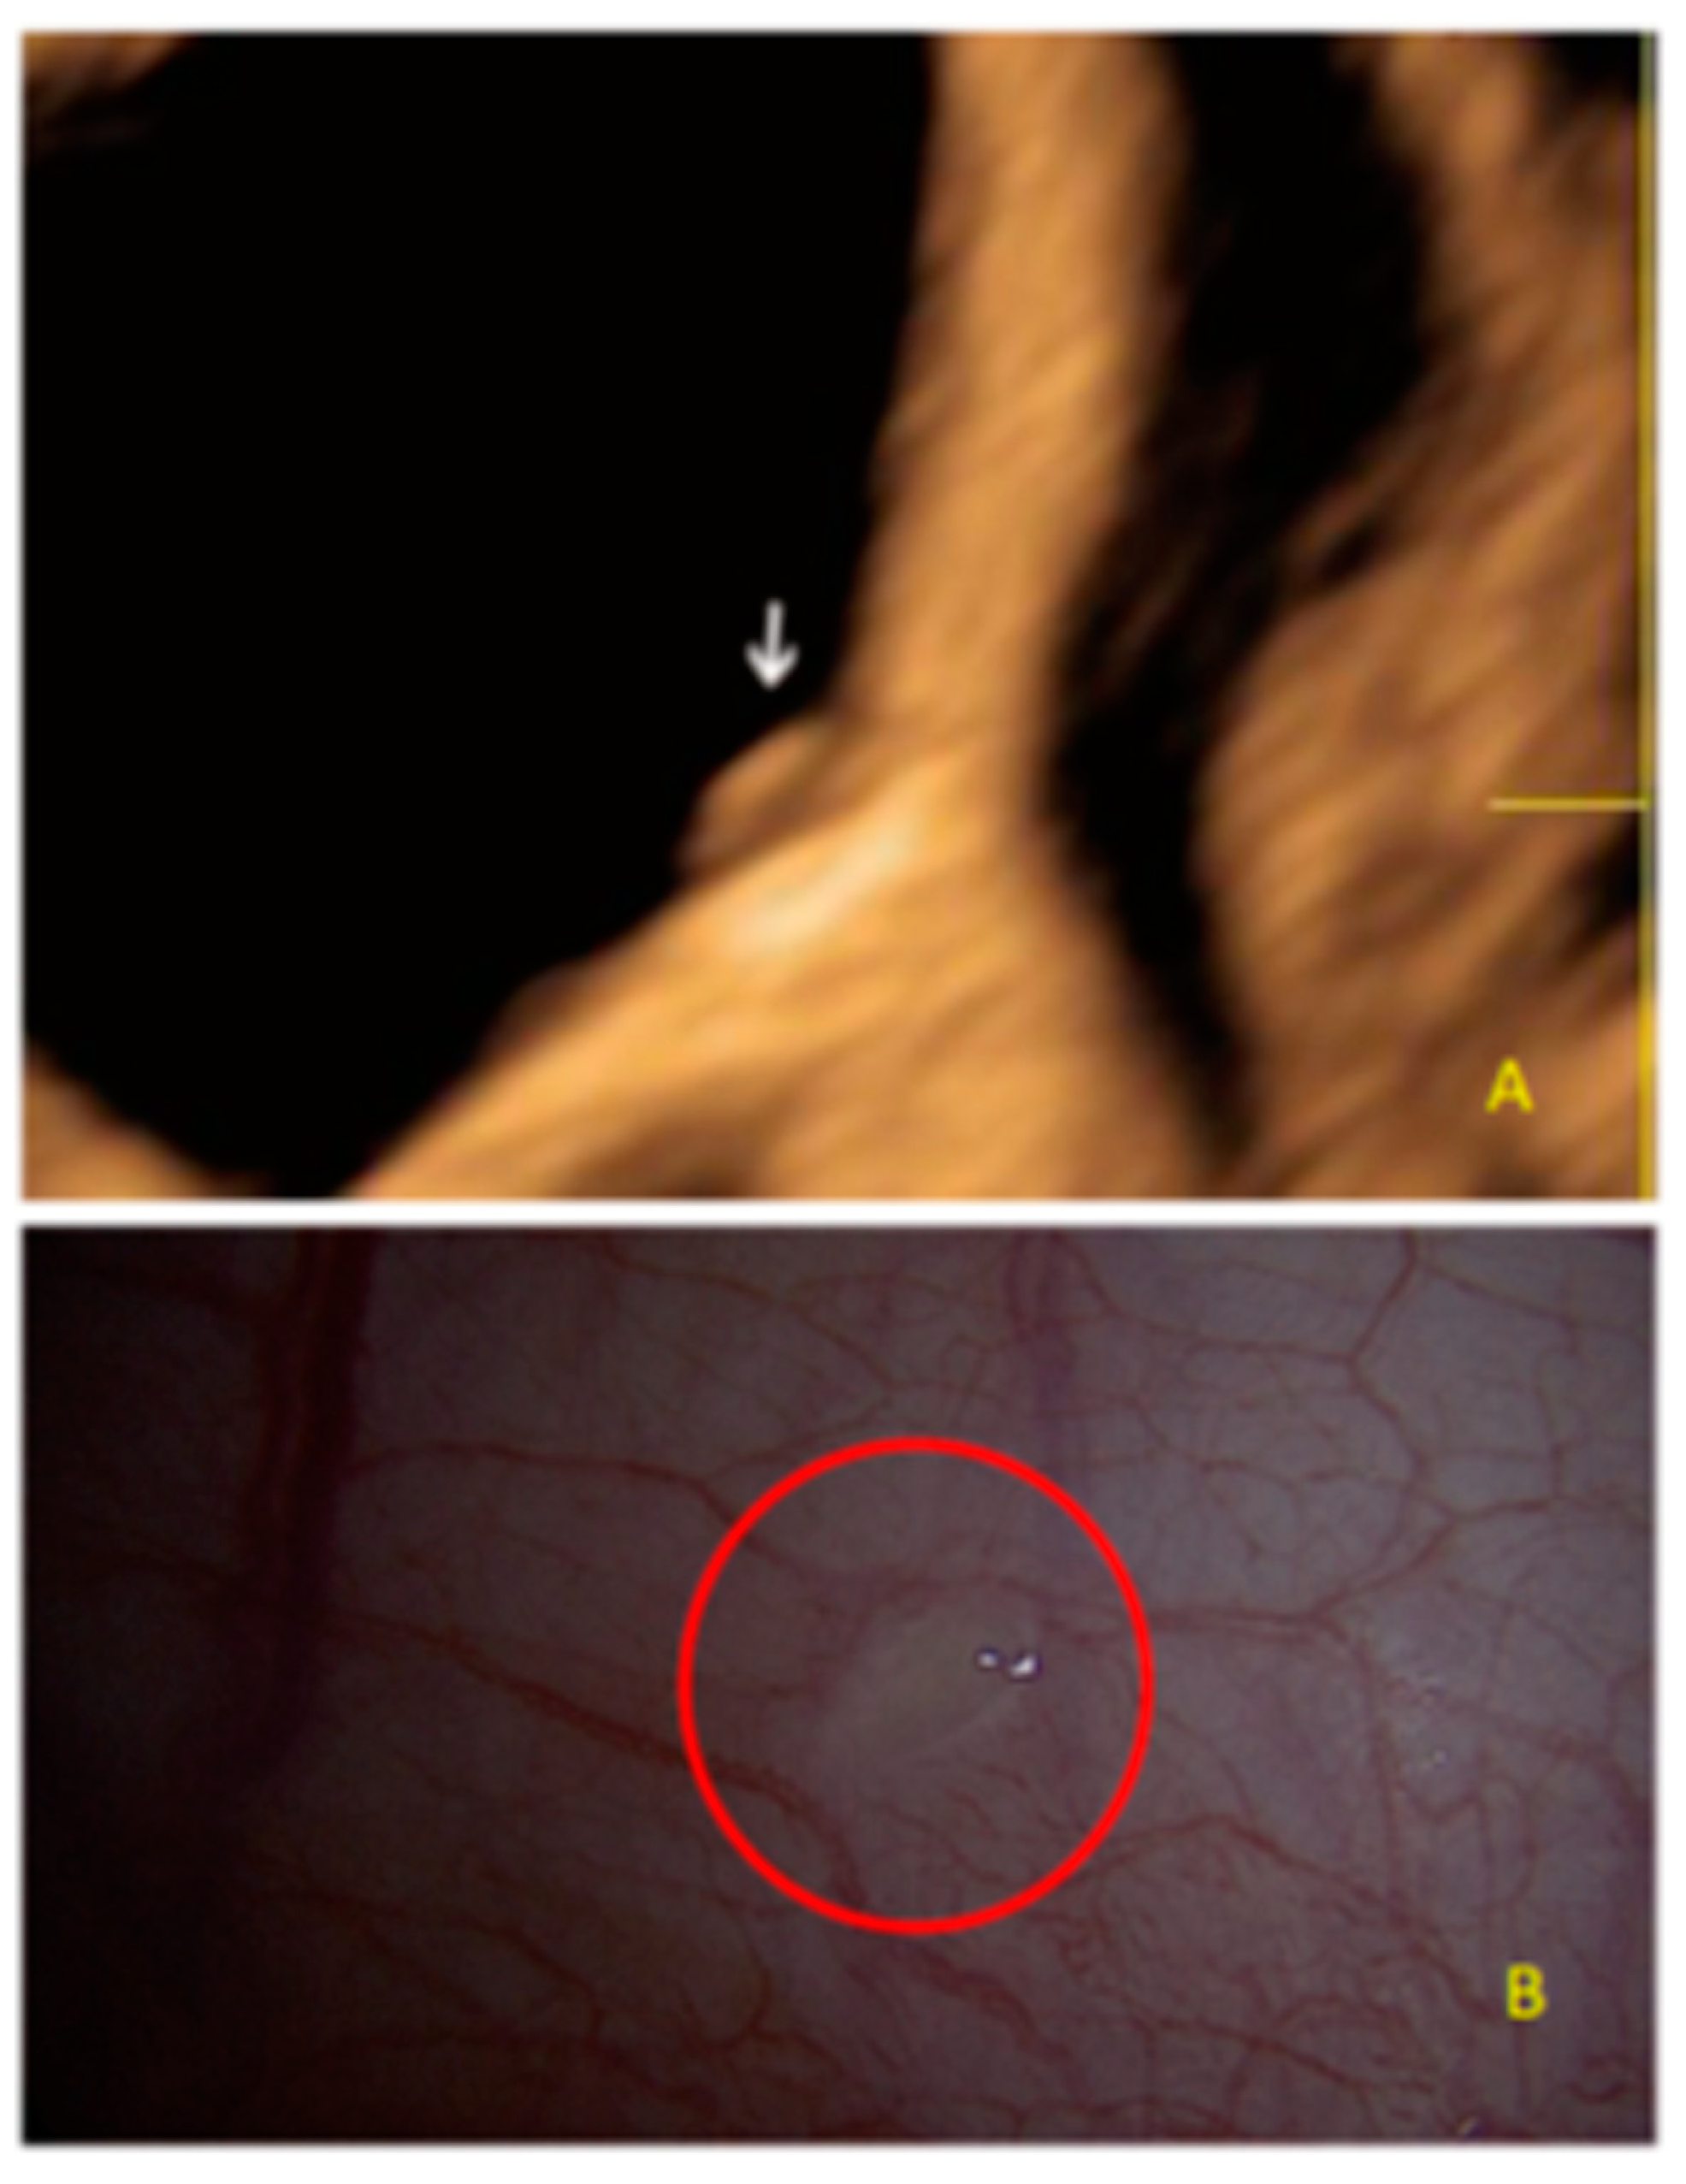

- The presence of hypoechogenic associated tissue (hypoechoic areas surrounding a small cyst area; we called this a “hat”). This tissue does not protrude or invaginate the peritoneal surface.

- The lesion may be convex, protruding from the peritoneal surface into the peritoneal cavity (we called this “bulging”), or it may appear as a concave defect in the peritoneum (we called this a “pocket”).

- The presence of hyperechoic foci (we called this a “pearl”).

- The presence of velamentous (filmy) adhesions associated to the lesion (we called this a “veil”).

3.1. Cystic Solitary Lesion